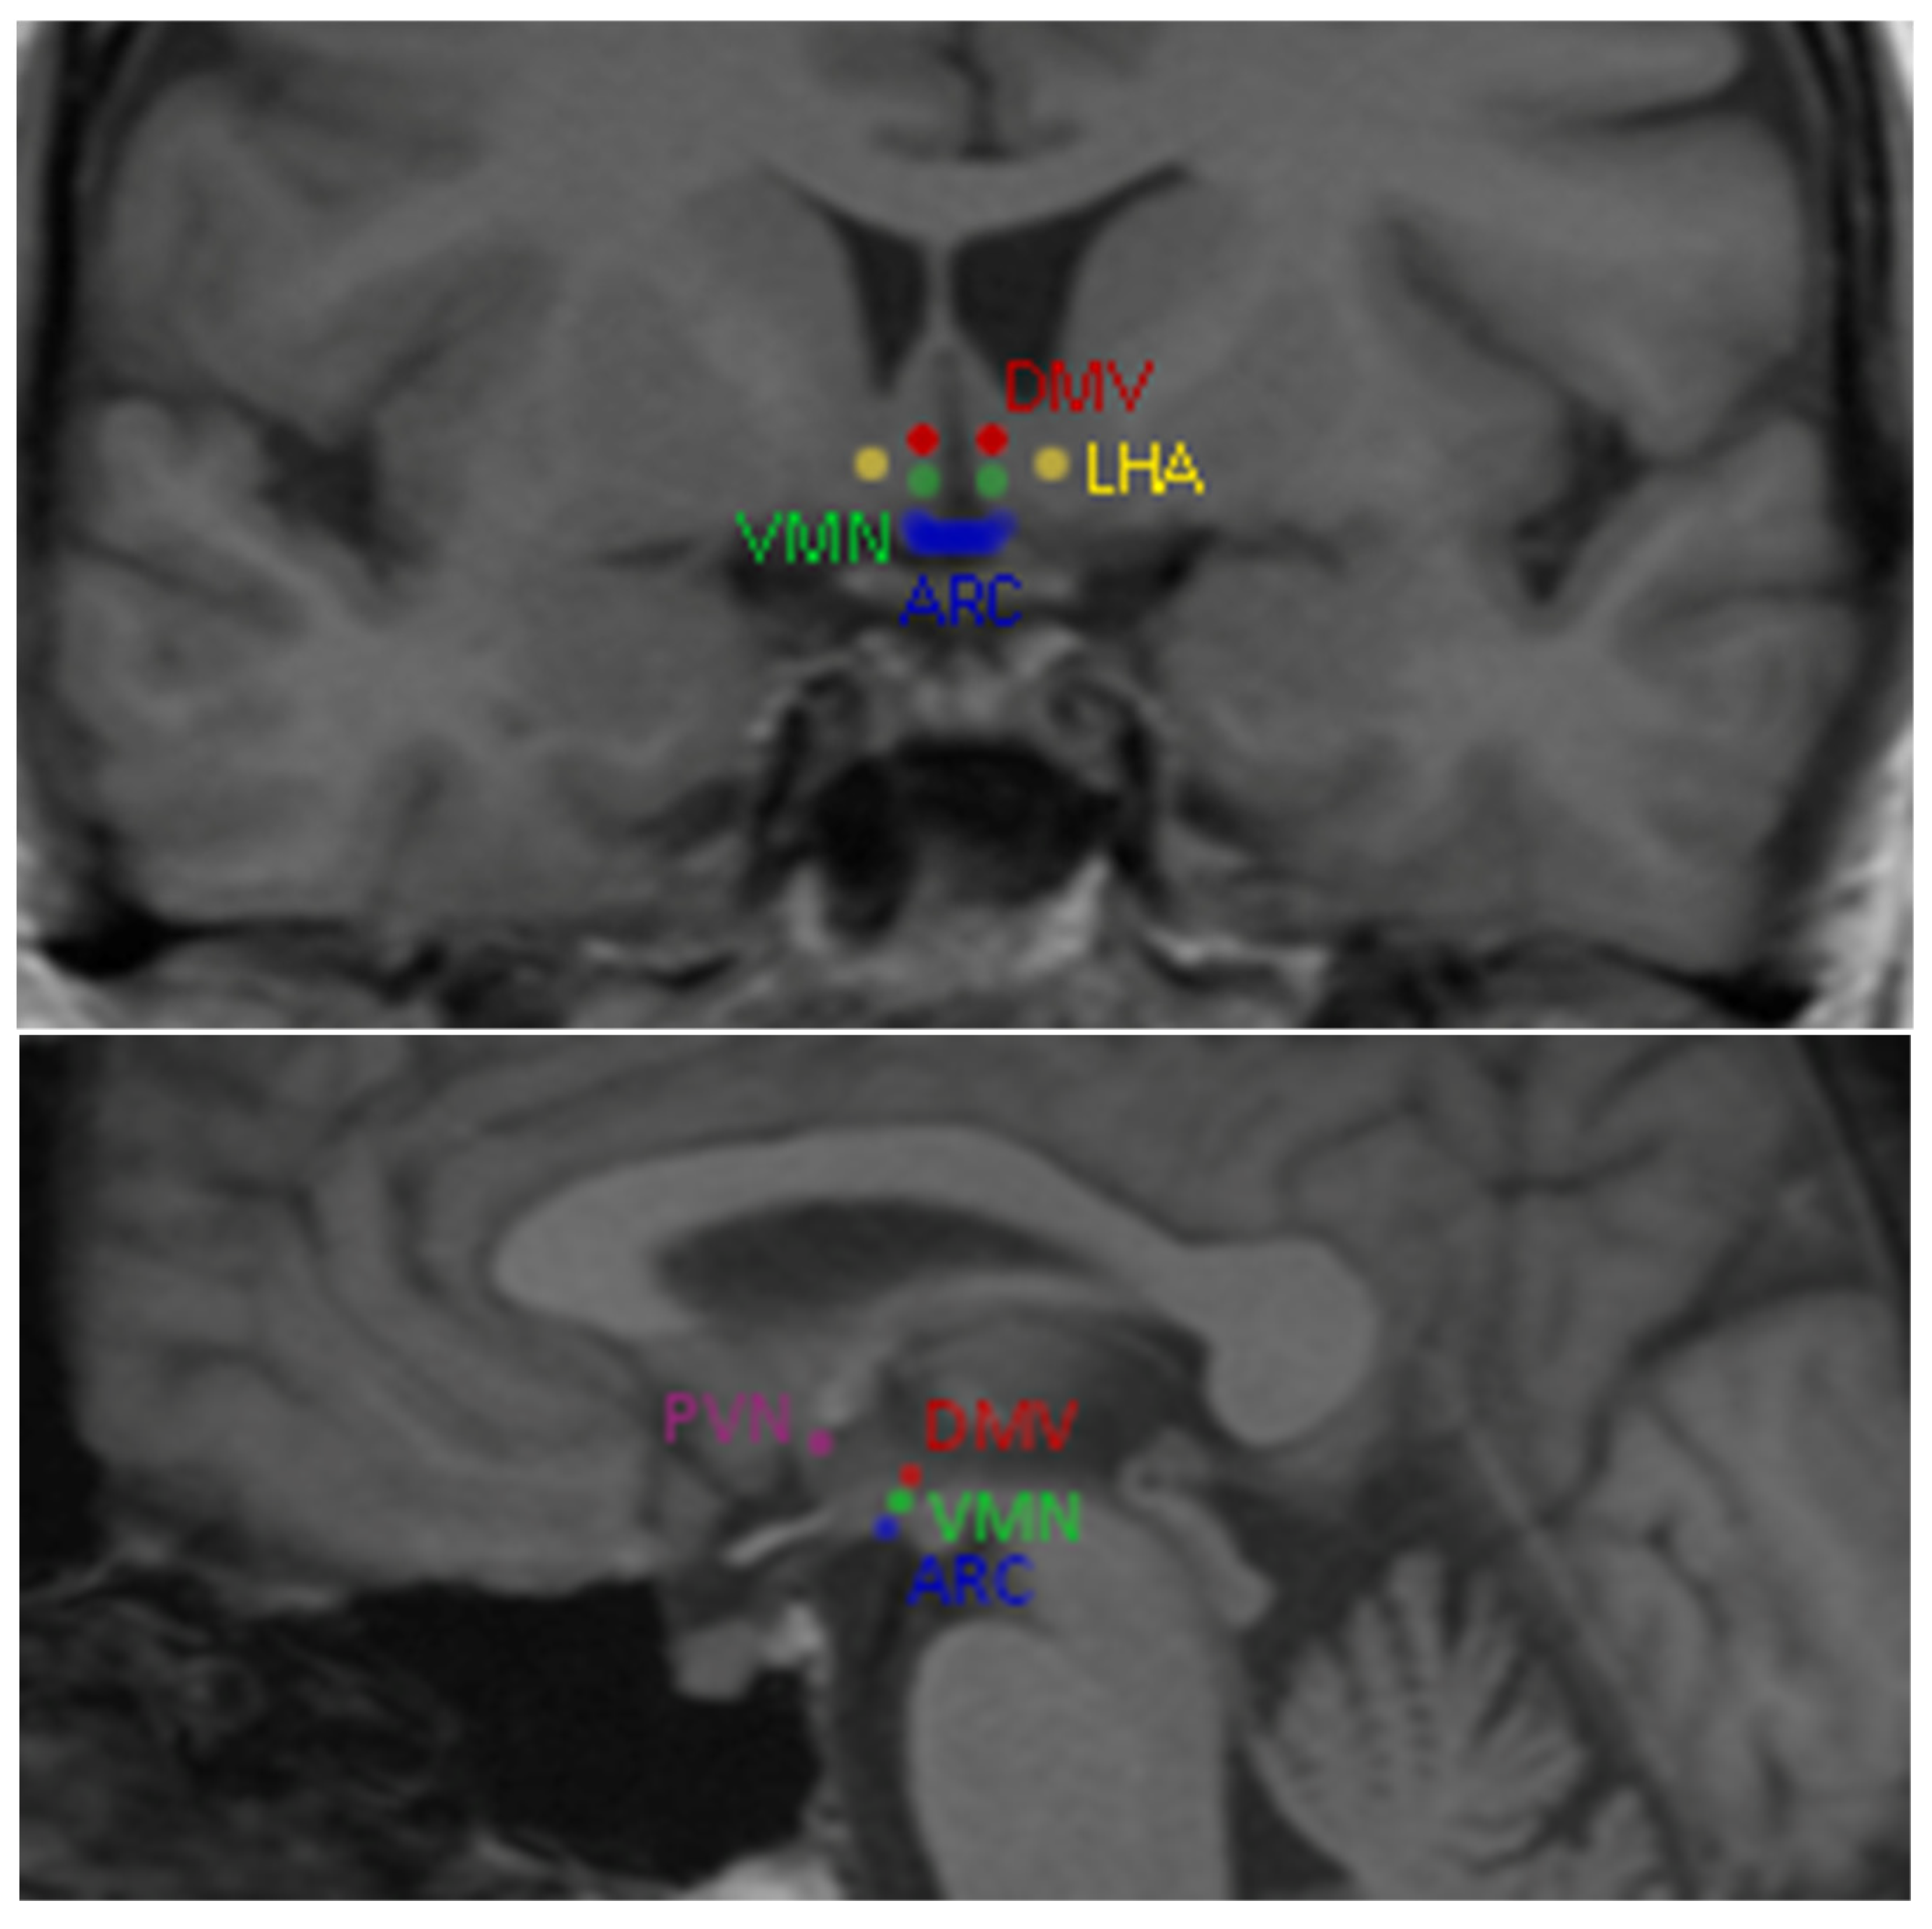

3.1.1. Homeostatic Brain System